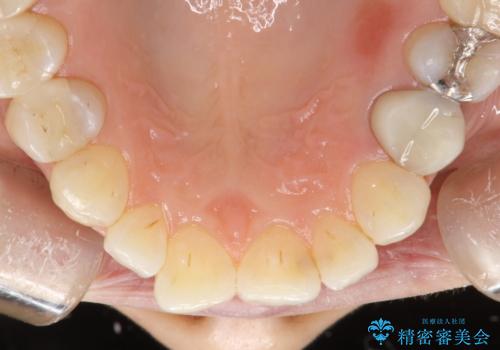

PMTCで歯と歯の間の細かいステインの除去

- 歯磨きでは取れない歯と歯の間の汚れが気になるとのことで来院されました。PMTC60分コースを行いました。

毎日丁寧に歯磨きをしていても、日常生活での飲食物などにより着色してしまうことはあります。PMTCでは、歯の表面の凸凹にミネラルを補給して、ツルツルの表面に仕上げます

歯科医院にて、適切な処置を行うことで、長期的に安定したお口の環境が作られます。まずはカウンセリングなどもおススメです。